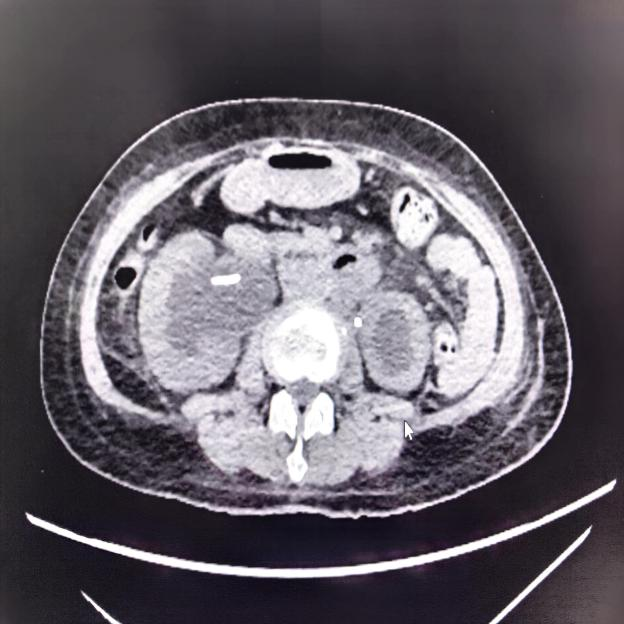

术前影像检查清晰显示患者双侧肾积水及输尿管受压

入院完善相关检查后,医师发现患者右侧输尿管受到肿瘤严重压迫,其承担主要排毒功能的肾脏产生的尿液完全无法流入膀胱。针对这一棘手情况,赵洪青、周骥带领团队经过审慎评估,最终为患者确定了“黑科技”金属温控输尿管支架置入术这一精准治疗方案。